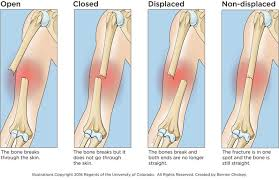

• Closed vs Open Fracture

closed - doesn't break the skin

open - break the skin + they cause more injury to local soft tissues, inc the periosteum, higher risk of infection

• Displacement

• Displaced vs Non-Displaced Fractures

non-displaced (stable) - fracture ends r aligned

displaced (unstable) - fracture ends r separate/misaligned